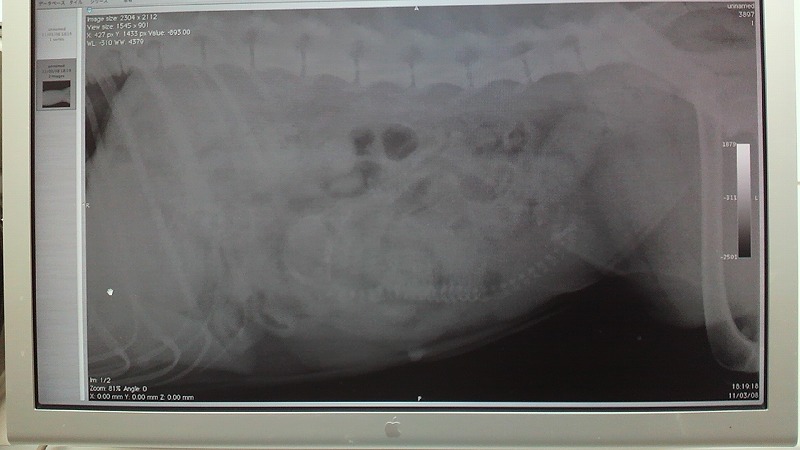

耳の温度一定せんなー